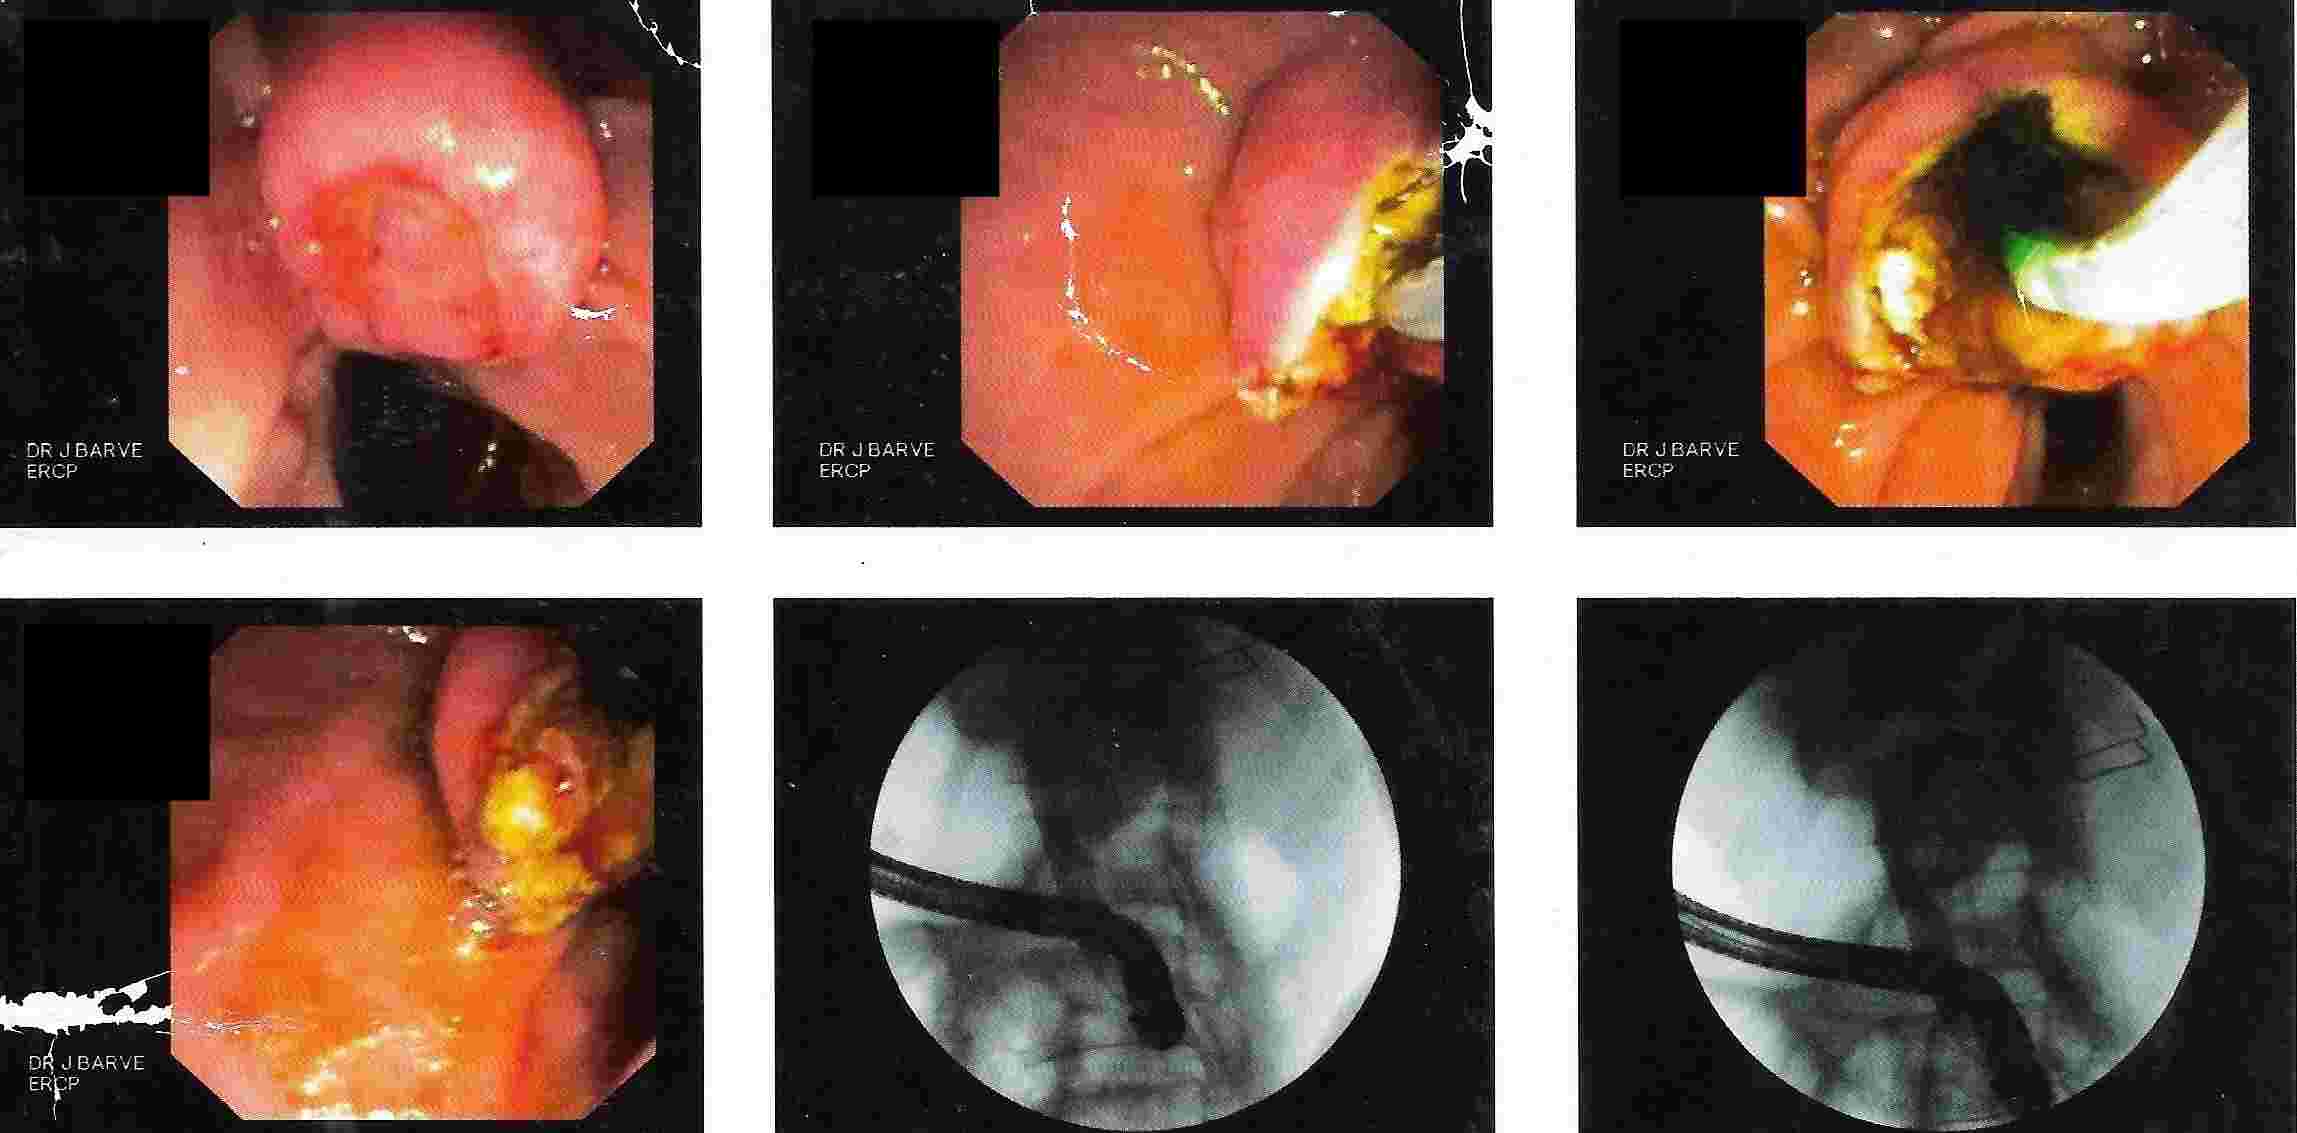

GALL BLADDER STONES TREATMENT

Endoscopic Retrograde Cholangio Pancreatography is an advanced endoscopic procedure related to

diseases of pancreas and biliary tree. Common indication for ERCP is jaundice due to obstruction

of biliary tube, which drains the bile from the liver into the intestine.

Obstruction can be due to a gallstone, which has slipped into bile tube and has blocked the bile tube.

These Stones can be removed by ERCP, without any surgery being involved.

This procedure is necessary if the patient has stones in the gallbladder and also in bile tube and

is always performed before Laparoscopic removal of gallbladder. Cancer of the gallbladder, biliary tree, pancreas,

duodenum or obstruction by lymph nodes can be responsible for jaundice and can be very effectively

treated by ERCP without any need for surgery.

This technique is important in these conditions as majority of the patients coming for jaundice are at an advanced stage of cancer and need palliative treatment to give relief from severe itching and jaundice. Infection or narrowing in the biliary tree can be treated by ERCP.

Common Biles Duct Stones

Common Biles Duct Stones

Cancer of the Bile Tube in Duodenum

Impacted Stone in Common Bile Duct

Chronic Pancreatitis is condition which can result in recurrent attacks of persistent and severe pain.

This can be due to presence of stones or narrowing of the pancreatic duct and can be treated by ERCP.

Pancreatic pseudocyst / collection of fluid is a complication of pancreatitis, which results

in abdominal pain, vomiting, fever etc. It is a serious condition which can be treated by ERCP.

Treatment of Chronic Pancreatitis by Stent

Most of the lesions of biliary system and pancreas were treated earlier by surgery with its own complications, but now with ERCP these conditions can be treated without any surgery and morbidity and mortality related to surgery, and as a cheaper option for surgery and has become treatment of choice for the same.